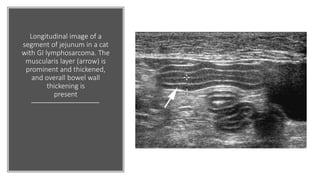

Longitudinal image of a

segment of jejunum in a cat

with GI lymphosarcoma. The

muscularis layer (arrow) is

prominent and thickened,

and overall bowel wall

thickening is

present

Longitudinal image ofa segment of jejunum in a cat with GI lymphosarcoma. The muscularis layer (arrow) is prominent and thickened, and overall bowel wall thickening is present